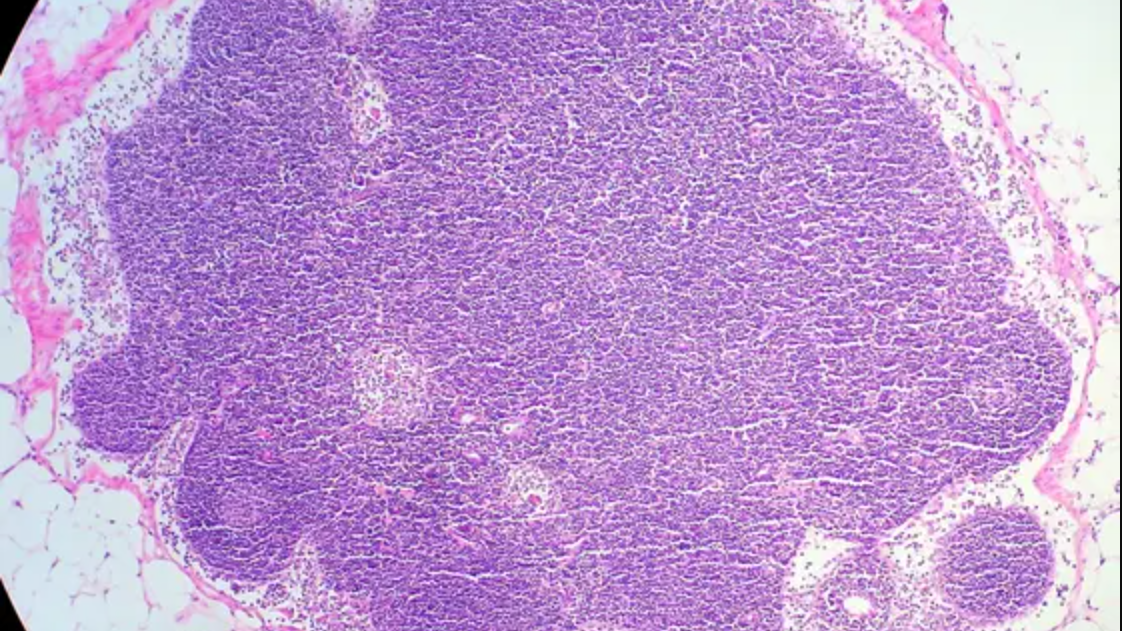

Study shows how lymph node architecture affects cancer growth

A new study maps the organisation of immune and stromal cells in lymph nodes and shows how loss of this organisation affects prognosis in certain lymphomas Summary Researchers from EMBL Heidelberg, Heinrich Heine University Düsseldorf (HHU), and Düsseldorf University Hospital (UKD) have succeeded for the first time in mapping the organisation of immune and stromal […]